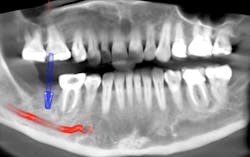

The old saying “you don’t know what you don't know” holds especially true in regard to 3-D radiology. You simply cannot gain the same amount of information from 2-D images. My main use for CBCT in the general dentistry practice is dental implant planning. In order to feel confident placing dental implants, I need this technology. I am able to identify cases that are appropriate for my skill level, as well as cases that are more difficult and should be referred. Whether a case will be tricky is not always obvious from a 2-D image and clinical exam. I also have not found a situation where less information was more beneficial than more information. I have never thought to myself, “I wish I didn’t have a 3-D scan of this patient.” Conversely, there were many times before buying my CBCT when I wished I had more than just a 2-D periapical (PA) or pan. The case shown in figures 1, 2, and 3 illustrates how the additional information CBCT provides aids in planning and placing dental implants.

Figure 3 tells a more complete story. The patient has a significant lingual concavity. I was unable to palpate the concavity clinically to realize its full extent. The 3-D image allows accurate measurement to the inferior alveolar nerve (IAN) and lingual concavity. It allows me to plan and place an implant of the appropriate length to avoid perforation of the lingual plate, which could lead to serious surgical complications.